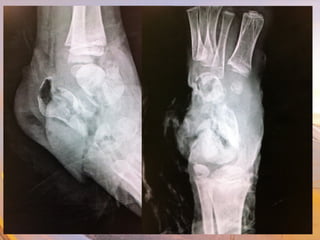

• Tarsals

• Calcaneus

• Talus

• Metatarsals

• Phalanges

• Mortise joint

• Medial & lateral

ligaments

• Lateral ligament &

fibular fx